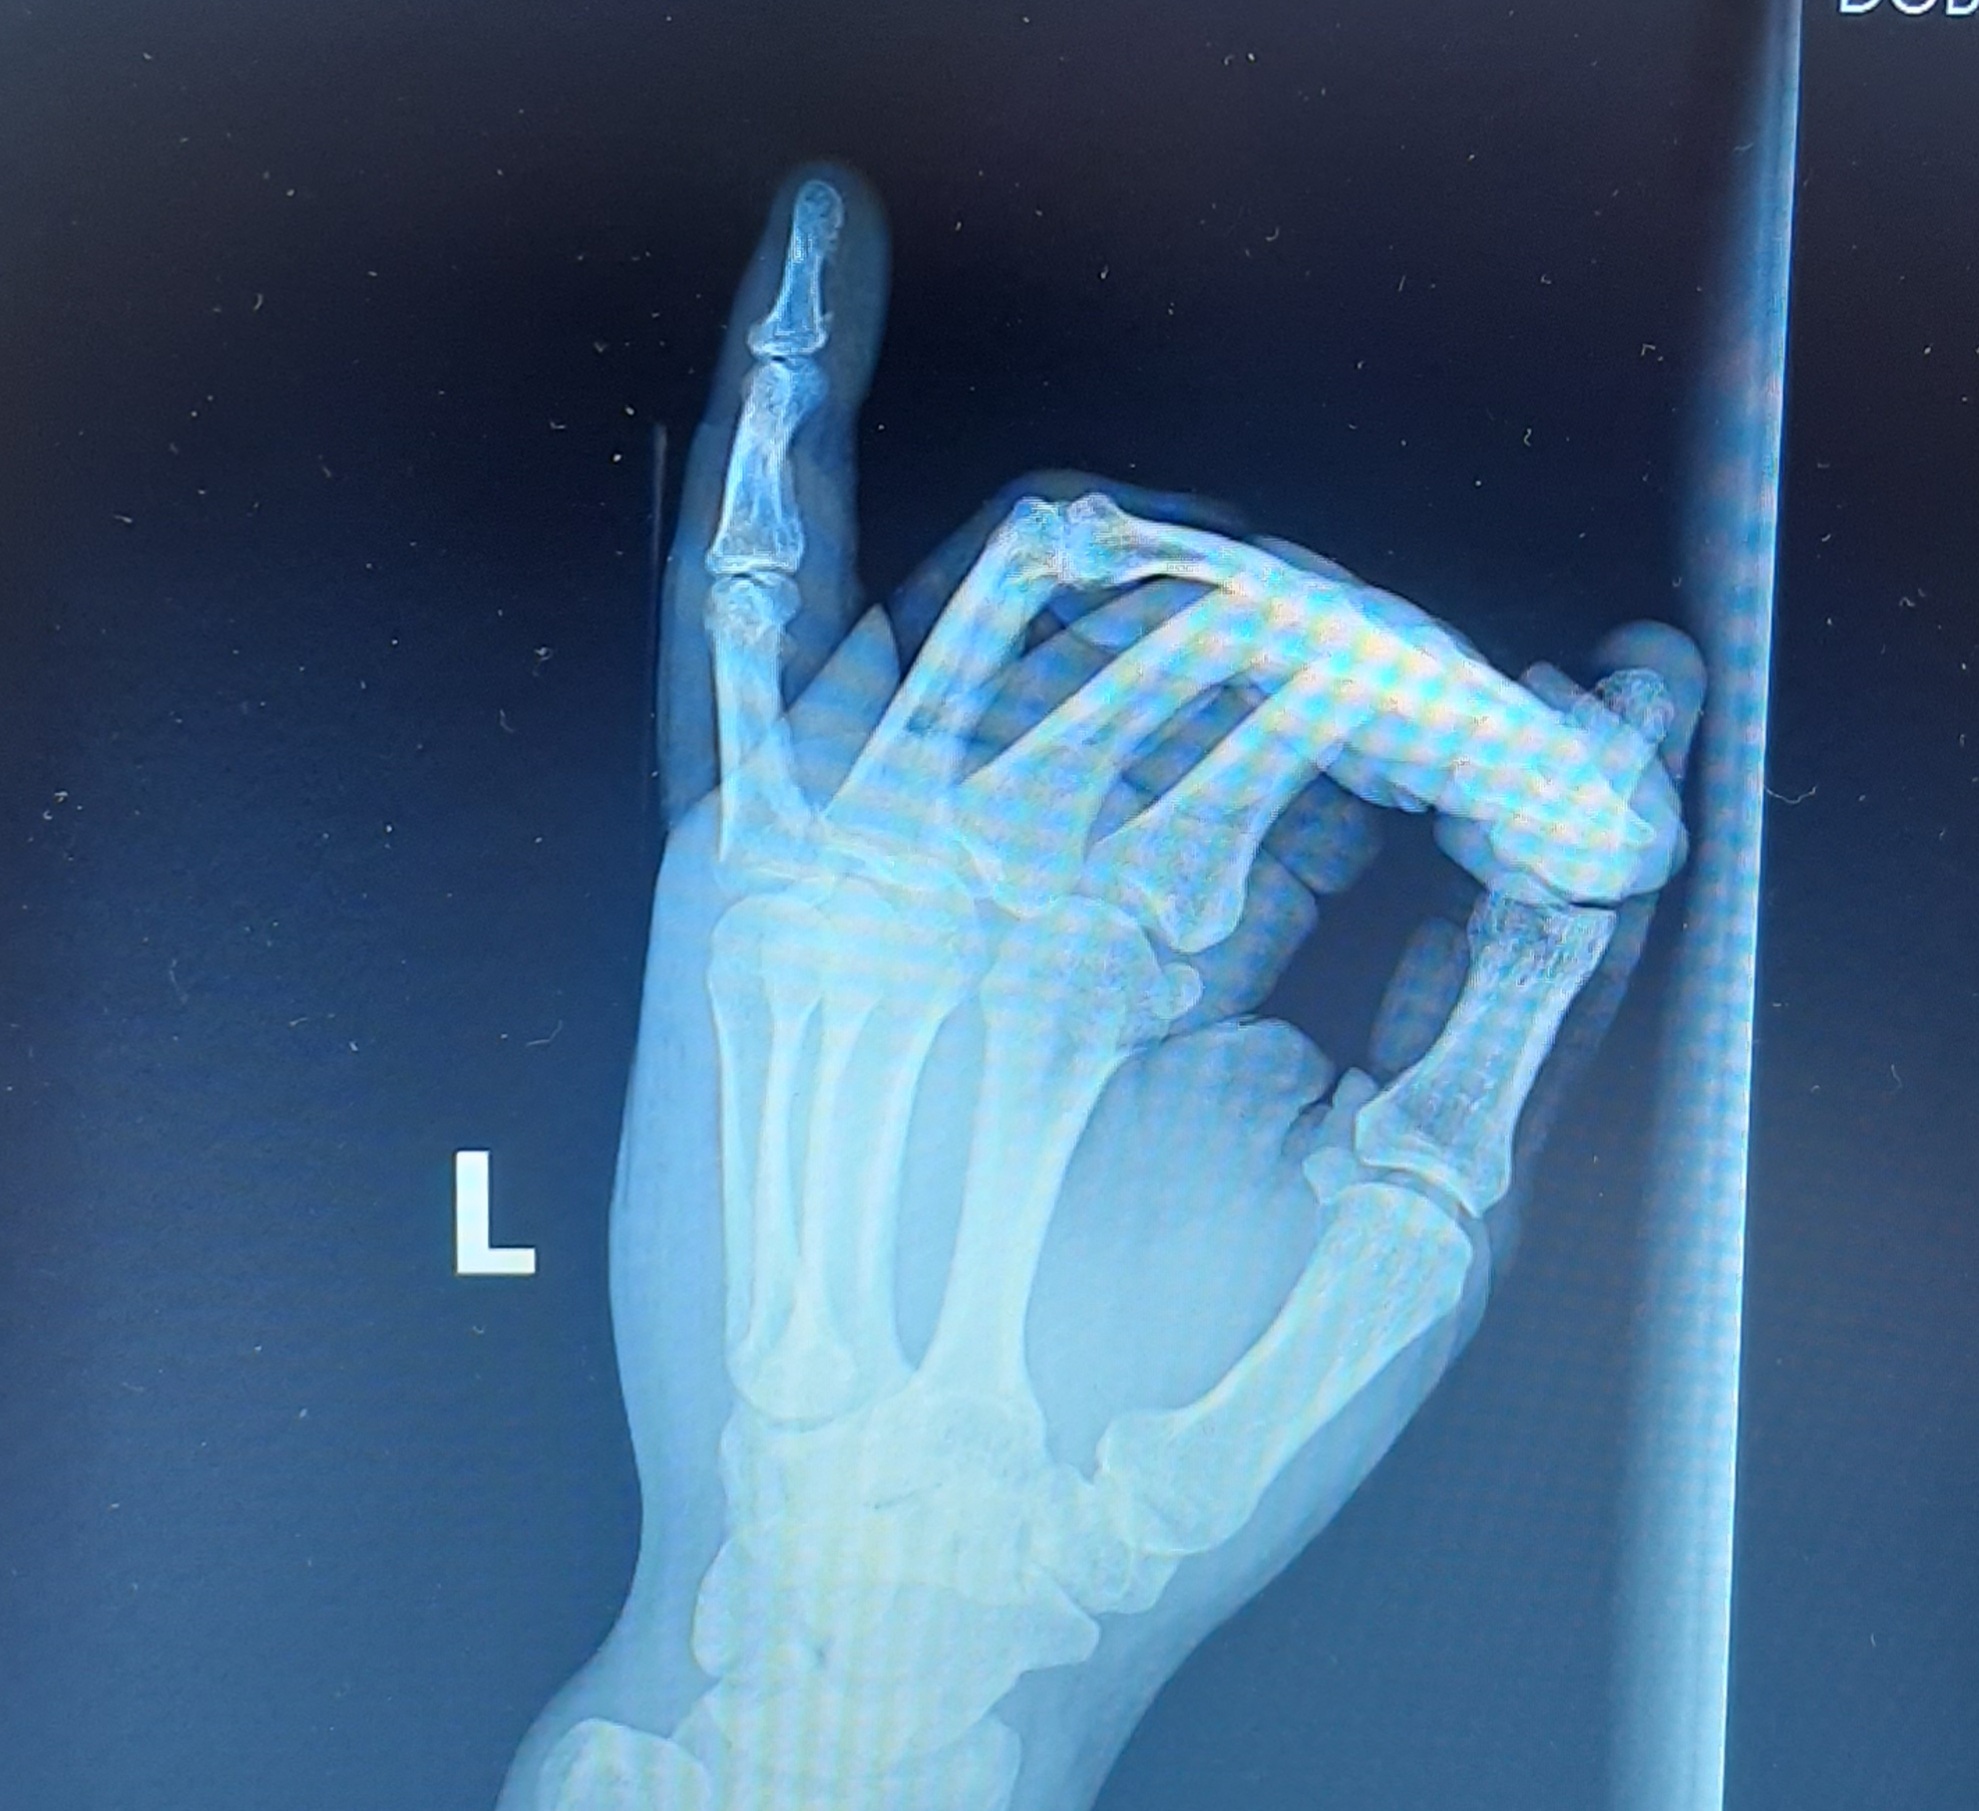

1 Netsmysla 2 года назад Посоветуйте плиз, так оставить или ещё куда обратиться? Сломал 5 числа. Только сегодня провели репозицию. (Вроде правильно написал). По сравнению со снимками от 5 числа мало что поменялось. Было: Стало: [моё] Медицина Перелом пальца Нужна помощь врачей Рентген Длиннопост Ещё 0